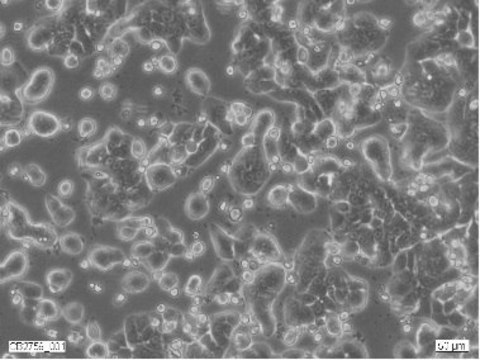

Morphology:

Epithelial

Human Caucasian colon adenocarcinoma

Isolated from a primary tumour in a 44 year old Caucasian female. Forms a well-differentiated adenocarcinoma consistent with colony primary, grade I. Tumours also form in steroid treated hamsters. Has the following HLA profile A1,3; B12,17; Cw5.